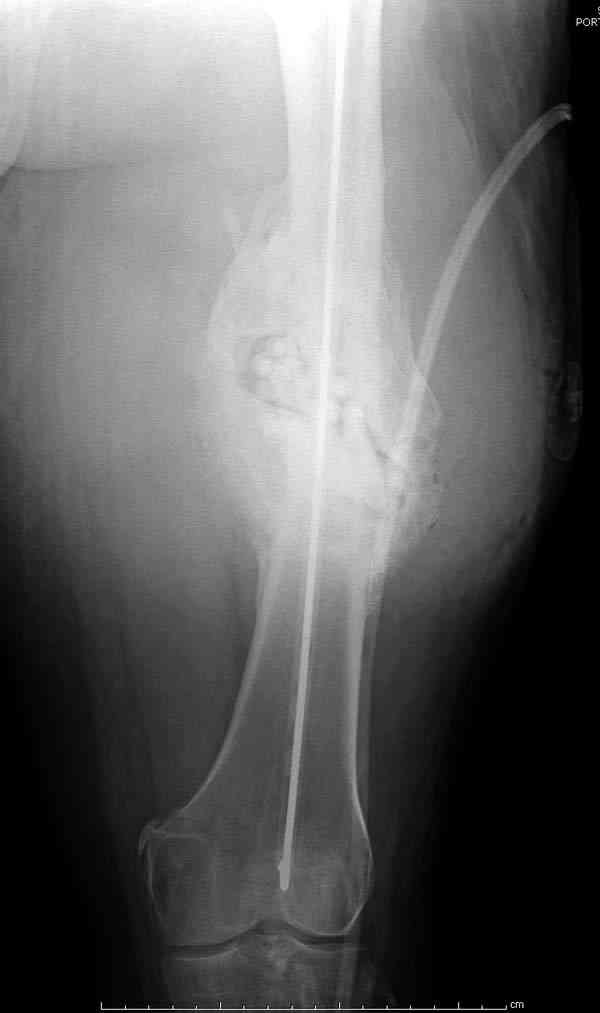

После нескольких некрэктомий, проведения аутодермопластики и заживдения ожоговой раны через 2 месяца после травмы произведен открытый остеосинтез левой бедренной кости штифтом и пластиной (деротационной) [image 01, 02]. Через 1 год и 7 месяцев после травмы у больного диагностированы ложный сустав и хронический остеомиелит левой бедренной кости. Произведено удаление металлических фиксаторов, секвестрэктомия и остеосинтез бедренной костивнешним двухплоскостным стержневым аппаратом [image 03, 04] .

Через 3 года после травмы констатировало отсутствие консолидации бедренной кости, сохранение признаков хронического остеомиелита (свищ в нижней трети левого бедра). Произведен демонтаж аппарата, реостеосинтез бедренной кости спице-стержневым аппаратом, некрсеквестрэктомия. В аппарате удалось лишь частично произвестиустранение углообразной деформации бедренной кости [image 05] .